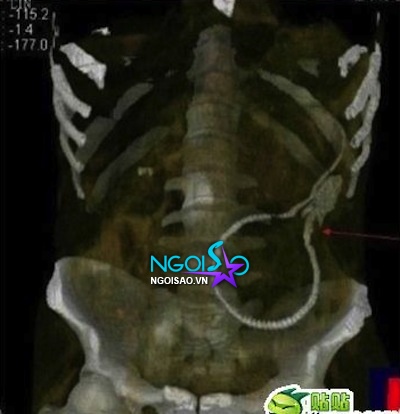

Đầu tháng 4 vừa qua, một sự việc kỳ lạ và oái oăm đã xảy ra tại Thuận Đức, Phật Sơn, Trung Quốc. Một người đàn ông hẳn do bắt chước theo những bộ phim người lớn, đã quan hệ với một chú lươn. Bất ngờ, lươn chui vào trong bụng qua đường hậu môn, gây vết thủng ở ruột.

Chú lươn có chiều dài 50cm, các bác sỹ phải mất cả buổi tối để đưa chú lươn ra ngoài.

Người đàn ông 39 tuổi, dùng lươn để tìm kiếm khoái cảm, không nghĩ rằng lươn chui vào hậu môn và di chuyển liên tục trong cơ thể.

HÌnh ảnh chụp X quang cho thấy chú lươn trong bụng bệnh nhân